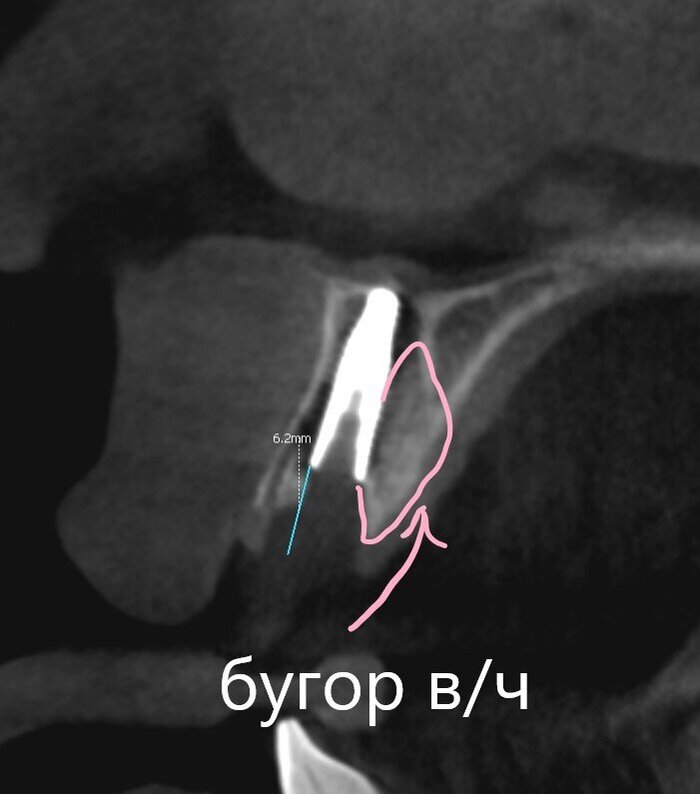

• удаление, костная пластика собственными тканями (бугор верхней челюсти), имплантация, сканирование со скан-маркером, временная клиническая коронка;

Имплантат 1.1 и костная пластика.

Ничего в этой области и в этой конкретной ситуации не сработает лучше, чем бугор верхней челюсти - лучшая донорская зона для забора кости. Минимальная усадка в ближайшей и отсроченной перспективе, приживаемость с вероятностью 99.99%.

Благо, у пациентки бугор есть. Только его наличие позволило провести имплантацию одномоментно с удалением зуба 1.1.